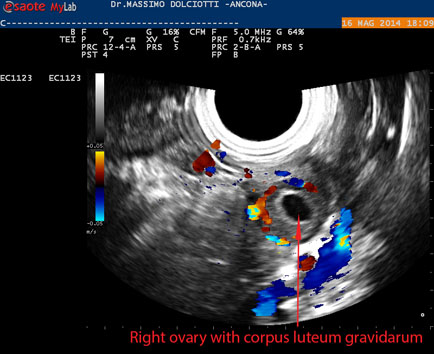

Data inserimento: 19 /05/2014Ecografia del: 16/05/2014 Strumento: Esaote MyLab 50 Gold - Responsabile Linea Cardio Esaote Regione Marche Dr. Franco Fabi Sonda: Endocavitaria Multifrequenza 4-8 MHz Età Paziente: F 27 anni Motivazione dell'esame: amenorrea. Beta HCG = 1.459 mUI/ml. Commento all'esame: le immagini ed il video documentano utero retroverso, con endometrio ispessito e presenza del sacco gestazionale delle dimensioni di 7,6 x 7,2 mm. All'ovaio destro presenza di corpo luteo gravidico con vascolarizzazione aumentata. Conclusioni: gravidanza alla quarta settimana di gestazione (Pregnancy at the fourth week of gestation). Potete esprimere le vostre osservazioni e commenti sul BLOG. Presentazione: Dr. Massimo Dolciotti - Ancona Elaborazione digitale: Andrea Dini - Ancona